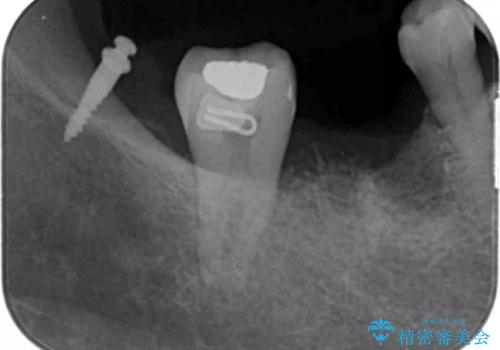

薄い歯質の歯牙に過大な負荷がかかり亀裂を生じ大臼歯分岐部に大きな骨吸収を認め、抜歯を余儀なくされる状態です。

抜歯を行ったのち前後の歯に軽度の動揺があるため、インプラントではなくブリッジによる補綴処置を行い機能回復を行いますが、近心傾斜した第2大臼歯をマイクロインプラントを用いた小矯正を行うことで歯軸方向を改善し、神経を温存した状態でブリッジ製作できるよう前処置を行います。